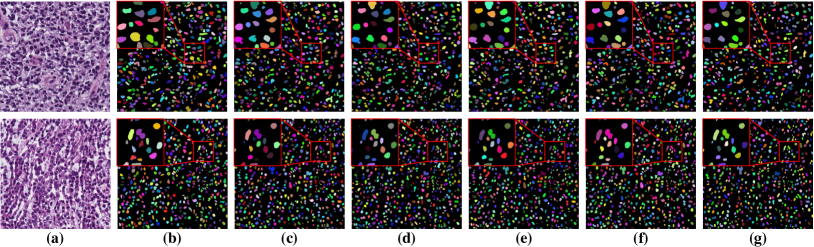

To investigate the impact of the proposed co-training and colorization methods, we validate the effectiveness of each module on the MoNuSeg dataset. Considering that Voronoi labels provide more shape supervision information than point annotation, we regard the model that jointly uses the point annotation and the Voronoi label as the baseline, and mainly evaluate the improvement of each module upon this baseline in Table III. Model A utilizes only point annotation and Voronoi labels with cross-entropy loss. For a fair comparison with co-training, we employ two separate models which have the same architectures for co-training and average the predictions of the two models in inference. Model B further adopts the cluster label. It can be seen that the cluster loss is beneficial in segmenting overlapping nuclei, improving the from 60.20% to 72.48% and the AJI from 43.01% to 51.77%, which indicates that simply using the point annotation and the derived Voronoi labels cannot provide sufficient supervision for the nuclei segmentation due to the lack of boundary and area information. However, the cluster labels generated by the -means algorithm cannot separate close nuclei which would introduce distraction to the training process, as shown in Fig. 1. To address this challenge, Model C utilizes the co-training strategy that the two models facilitate each other in a bootstrapping way to eliminate the distraction brought by the cluster labels. As expected, co-training brings a consistent improvement in all metrics, including an 1.19% increase to AJI. We believe that co-training compensates for the loss of supervision information in the uncertain regions in the cluster label, and the probability map with EMA by another model provides more precise and robust supervision in the nuclei boundary. Visualization of the segmentation results can be found in Fig. 3, and it can be seen that with the co-training strategy, the model can achieve more accurate results, especially in the nuclei boundary area. Model D involves colorization as a proxy task to implicitly learn to be self-aware of the nuclei boundary. Instead of directly coloring the H-component (Fig. 4(a)) to the H&E map (Fig. 4(d)), we use the segmentation probability map (Fig. 4(b)) as the input of the colorization network, which can help us to boost the segmentation accuracy. The experimental result shows that integrating the colorization tasks could not only improve the by 1.54% and AJI by 3.24%, but also promote Acc by 0.18% without dropping F1 score, proving that the colorization task has a significant guiding effect on nuclei segmentation. In Fig. 4(c), the improvement of colorization in the nuclei boundary area can also be observed. In general, the four modules used in our method have complementary advantages. By minimizing the weighted sum of the four losses, the proposed framework can distinguish between nuclear and non-nuclear to the greatest extent.

In clinical practice, due to the time constraint, pathologists cannot exactly put the annotation point at the center of a nucleus. We carry out experiments to investigate the impact of point perturbation to segmentation performance. To simulate the actual annotations, we perform a uniform random shift within different ranges of the generated point annotations. Several examples are shown in Fig. 5 illustrating that the small shift makes the points not too far from the center, but there are still some cases that the points are close to the boundary or even outside the nuclei. The number of points falling outside of the nuclei increases as the shift increases. Fig. 6(a) gives a quantitative illustration that as the shift increases from 0 to 20 pixels, the ratio of point annotations being within the nuclei decreases from 98.66% to 39.54%. Obviously, the offset of the points reduces the quality of the coarse labels, especially the accuracy of the nuclei in cluster labels is reduced from 85.46% to 49.72%. We train the models with the point annotations obtained by different shifts and calculate two object-level metrics. As illustrated by the changing trends of and AJI versus the shifts in Fig. 6(b), the segmentation accuracy of the proposed method degrades more gradually than that of the cluster results. The four-pixel shift only result in 1.38% drop in and 1.15% drop in AJI to the segmentation results of the proposed method, but 2.75% drop in and 3.27% drop in AJI to the cluster results. Even though the eight-pixel shift makes about one fifth point annotations not in the nuclei, the segmentation performance can still reach 70.75% in and 50.72% in AJI, respectively, which verifies the robustness of our method to point annotation offset. We believe that the robustness owes to the label propagation which refines the coarse labels to compensate for the impact of the offset. In clinical practice, professional pathologists will ensure the quality of point annotations, thus avoiding performance degradation caused by excessive offset. Some nuclei instance segmentation results with different shifts of point annotation are presented in Fig. 8. The robust instance segmentation performance lays the foundation for further counting and morphological feature extraction of nuclei on pathology images.